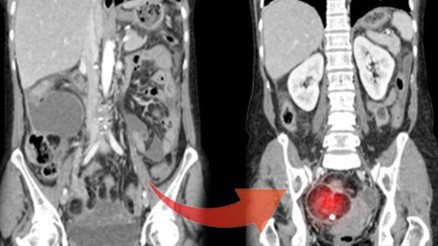

#SağlıkSevgili Hürriyet okurları... Ketojenik diyet yüzyıllar önce epilepsi tedavisinde kullanılan bir beslenme biçimi. Son yıllarda yapılan çalışmalar ketojenik diyetin bazı kanser türleri üzerinde olumlu etkileri olabileceğini düşündürmüştür. Ancak bu konuda internette çok fazla bilgi kirliliği var.